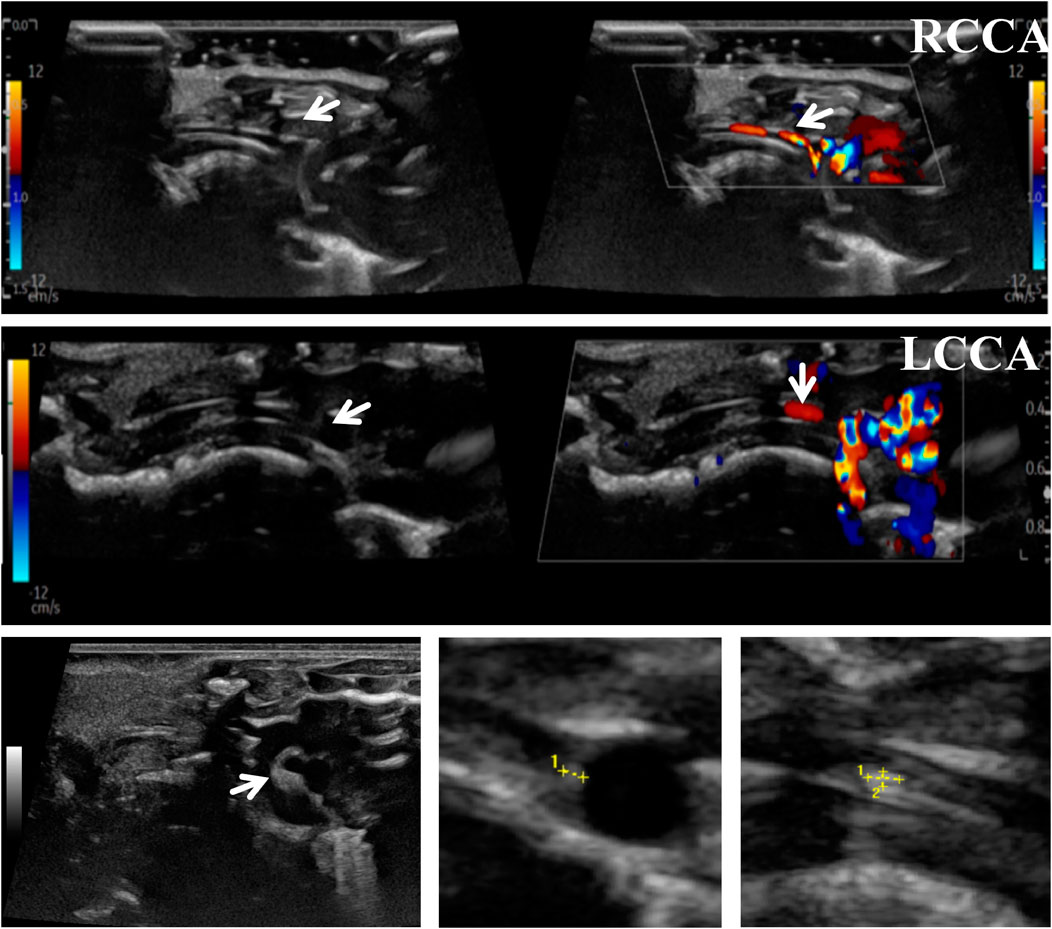

To accurately predict the success rate of the animal models and the effects of drug interventions, multi-modal ultrasound was performed prior to the study endpoint. The results showed that the right common carotid artery (RCCA) and left common carotid artery (LCCA) of mice can be clearly detected by ultrasound. AS-plaques on the arterial walls of the mice were also successfully detected (Figure 2). With the contribution of ultrasound, the plaque detection rates in each group were 0/10 (0%) in the normal control group, 8/10 (80%) in the model group, 3/10 (30%) in the LP-FDT treatment group, and 2/10 (20%) in the atorvastatin treatment group (data not shown). Next, blood flow velocity was analyzed by specific ultrasonic module, and the resistance index (RI) of blood flow was calculated using the formula: RI=(PSV-EDV)/PSV (note: PSV: peak systolic velocity; EDV: end diastolic velocity). As shown in Figures 3, 4, the resistance index of blood flow in the RCCA, LCCA, RICA, and LICA was significantly higher in the model group compared to the normal control group (P < 0.01). Compared with the model group, LP-FDT treatment significantly reduced the resistance index of the RCCA and LICA (P < 0.05). Based on the ultrasound results, we accurately selected seven mice for follow-up experimental studies.

Figure 3. Blood flow velocity and blood flow related indexes of four carotid arteries (RCCA, RICA, LCCA, LICA) detected by ultrasound.